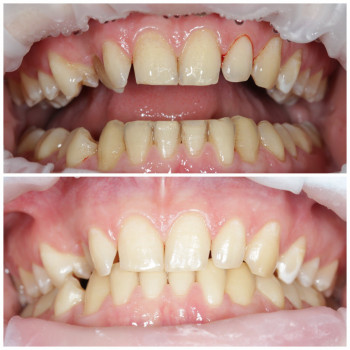

Лікування пародонтиту від 1 до 4 ступеня тяжкості у Хмельницькому Пародонтит – це запальне захворювання ясен і тканин, що утримують зуби. Без лікування воно прогресує від початкового нальоту й кровоточивості до серйозної втрати кісткової тканини та рухливості зубів. У нашій клініці ми проводимо комплексне лікування пародонтиту будь-якої стадії – від 1 до 4 ступеня тяжкості. ✔️ 1 ступінь – професійна гігієна, усунення нальоту, навчання догляду ✔️ 2 ступінь – кюретаж ясенних кишень, лікування запалення ✔️ 3 ступінь – комплексна терапія, шинирование, відновлення тканин ✔️ 4 ступінь – хірургічні методи, імплантація та протезування при втраті зубів Ми використовуємо сучасні методи: ультразвукову чистку, Air Flow, закритий кюретаж. Регулярне звернення до пародонтолога дозволяє зупинити прогресування хвороби, зберегти власні зуби та повернути здоров’я ясен. 👉 Запишіться на консультацію та лікування пародонтиту у Хмельницькому – відновіть здоров’я ротової порожнини на будь-якій стадії захворювання!